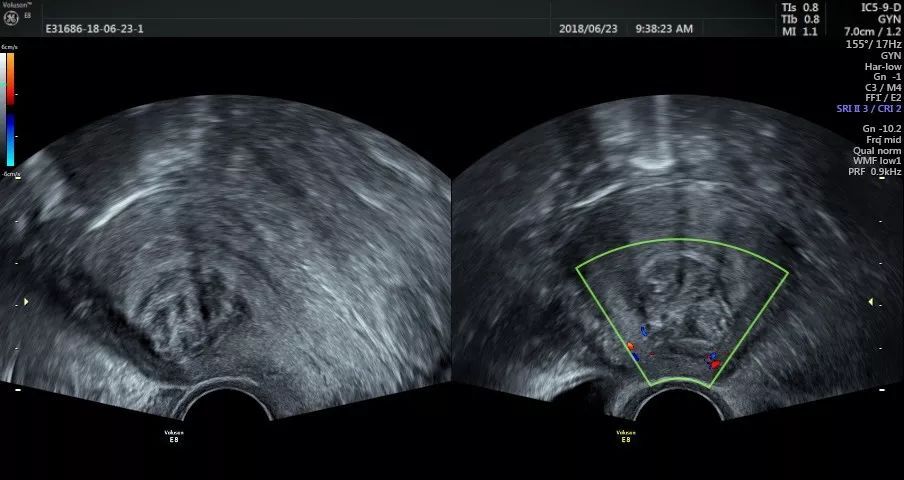

2、子宫肌瘤5厘米要手术吗?

如果肌瘤发展的很快或者严重压迫到其他器官则需要,其他则可以保守调理

7、子宫肌瘤多久需要复查一次?

半年或一年,因为有些肌瘤会慢慢发展、变大、所以需要及时观察以防恶化。